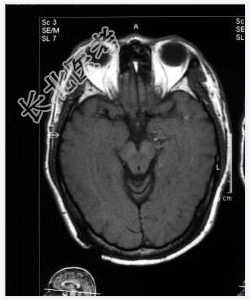

- [材料题] 患者,男性,52岁,间隙性发作情绪激动、乱语2年。一月前外院CT提示左海马高密度影,性质待定。做头颅MRI检查。